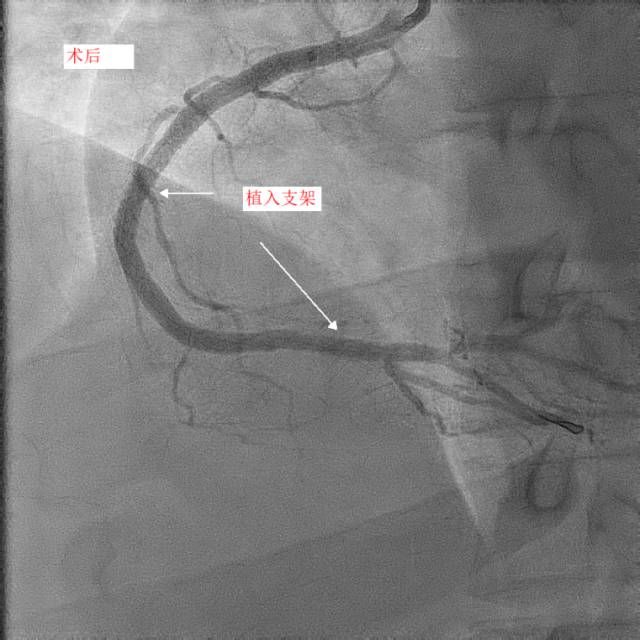

第二天,小天和父亲同一天接受冠脉造影和手术治疗,冠脉造影进一步明确了:小天冠状动脉回旋支完全堵死、前降支90%堵塞,而右冠状动脉也仅有一丝血流通过。造影中医生发现,小天的血管狭窄已经有一段时间,其中的右冠状动脉已经产生了侧支循环。随后医生在患者右冠状动脉里放入了两个支架,恢复了血流。

康慧元医生说:“患者的三条心脏血管都严重堵塞,很容易发生急性心梗甚至猝死,手术先开通慢性堵塞的右冠状动脉,保证心脏有足够的血流。”

两天后,医生再次手术解决了左前降支的问题,至于回旋支因为先天血管发育较小,可暂时观察,后续再处理。